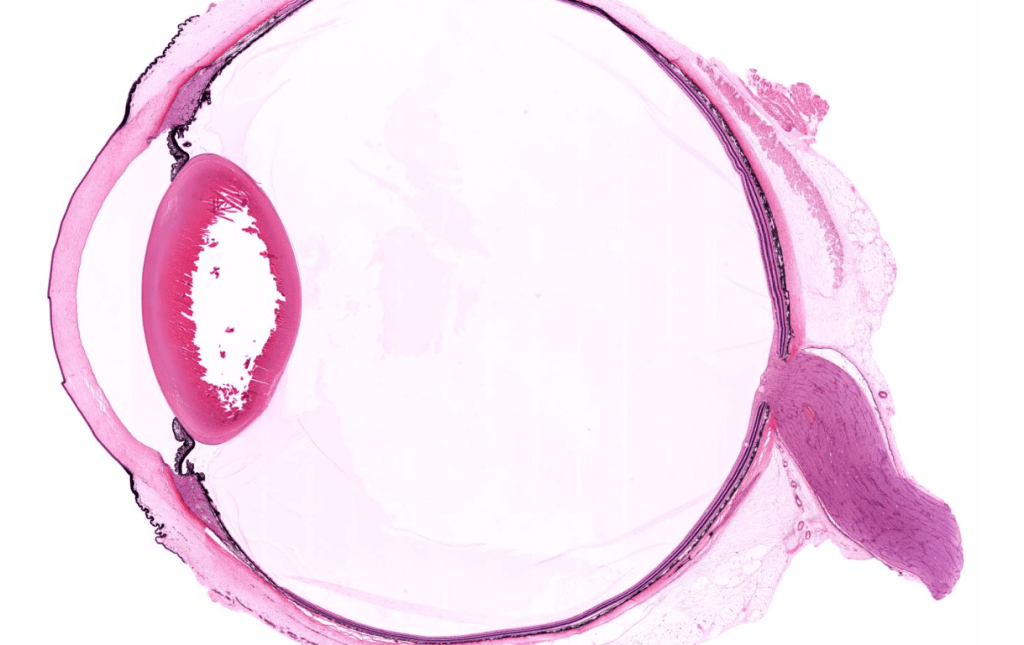

CÓRNEA

Consta de 5 capas:

1. Epitelio corneal

2. Membrana de Bowman

3. Estroma corneal

4. Membrana de Descemet

5. Endotelio corneal

IRIS

CUERPO CILIAR

RETINA

CRISTALINO